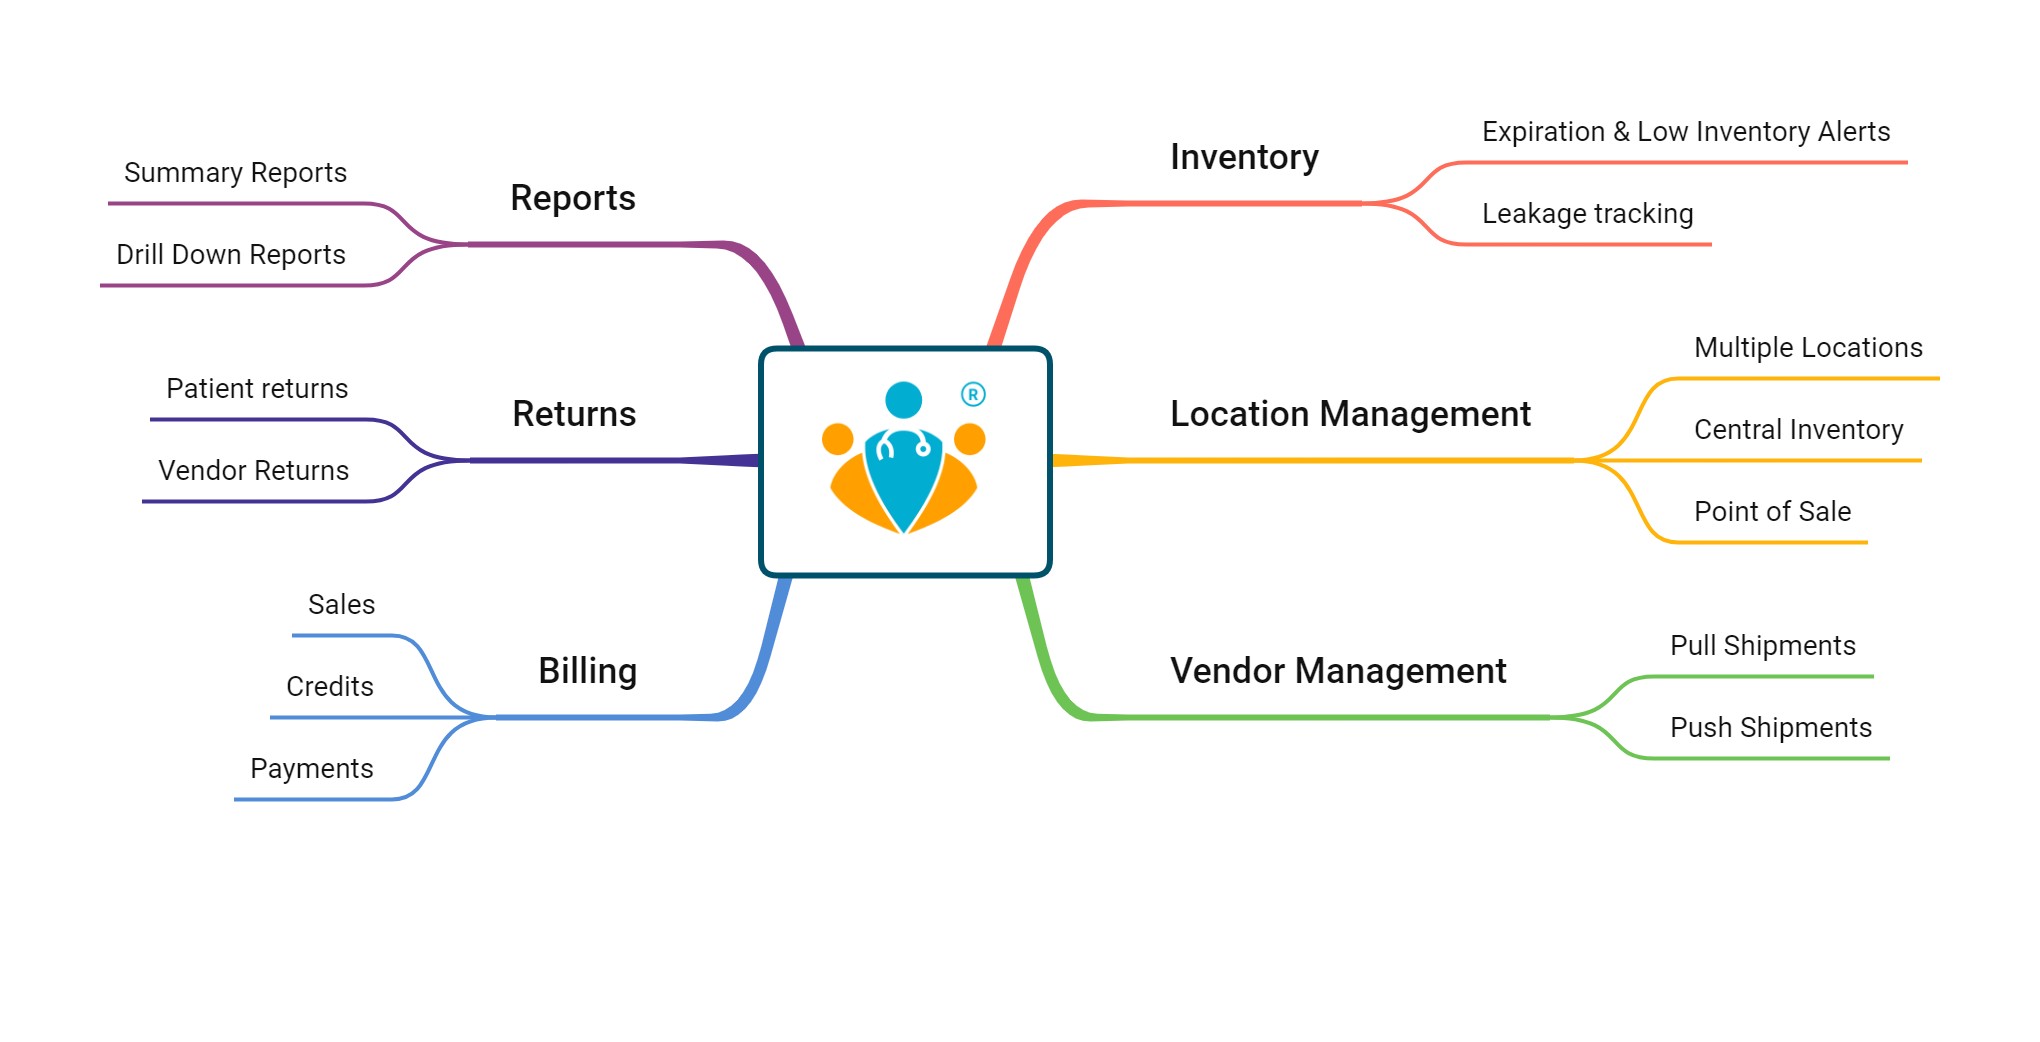

TinyMedic's comprehensive Pharmacy Management solution offers end-to-end features - Prescription Processing, Billing, Payments, Inventory, Stock Auditing, Accounting, Analytics, and Reporting.

Now automate your workflows for efficiency, accuracy, and patient-centric service. Further, you can track your customers' purchase history and prescriptions to plan for timely medicine refills.

We serves the need of various pharmacies :

With our solution, you can manage and track all the IP pharmacy orders and auto-update them to the hospital's medical records and the patient's PHRs. We helps you handle your OP orders faster and more efficiently with our support for e-prescriptions. IP order or an OP order, Our cloud-based solution is integrated with the patient's application for consistent and streamlined medication management.

Depending on the services you offer to the patients - OP, IP, in-house Diagnostic Lab & Pharmacy- We cater to your specific needs through our modular solutions to minimize costs for you. TinyMedic offers Modular solutions to cater to independent Pharmacies, Pharmacy Distributors, Labs, Single Speciality Clinics, Multi-speciality hospitals, and chains of Multi-speciality hospitals looking to improve their efficiency and enhance patient engagement.

Hospitals, Clinics, Labs, and pharmacies play different roles in healthcare delivery. Each interacts differently with the patients and hence needs unique features to cater to the needs of the patients. TinyMedic's Modular solution provides specific features for each entity while allowing hospitals, labs, and pharmacies to integrate seamlessly to serve patients through one unified platform. By integrating our modules into a single system, hospitals, labs, and pharmacies can reduce costs while improving patient care.

Additionally, an integrated platform like TinyMedic makes it easier for healthcare professionals to access and manage data from multiple sources quickly and efficiently. For example, Our Hospital Module can manage patient records, billing, scheduling, and other administrative tasks. Similarly, Our Lab Module can track laboratory tests and results, while our Pharmacy Module can help pharmacies manage their inventory and orders.